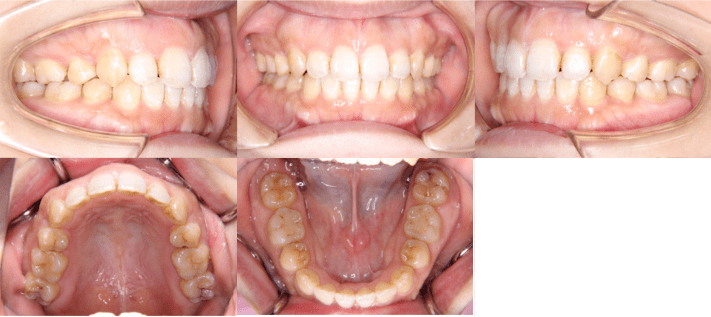

After

治療後

• 初診時年齢:28歳4ヶ月

• 主訴:前歯のかみ合わせ

• 診断:開咬

• 治療内容:小臼歯4本を抜歯した後に、インビザラインを使用して主訴である開咬の改善を行いました。

• 治療期間:2年

• リスク:矯正治療による歯の移動に伴う痛み、歯根吸収、虫歯

• 費用:80万円